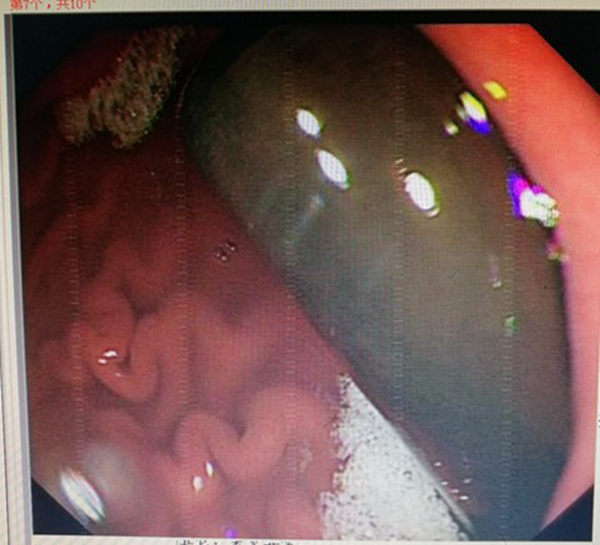

一提到做胃镜,很多人都望而生畏。有的甚至信誓旦旦地下决心,这一辈子再也不受这个罪了。患者对胃镜究竟有多么害怕,都担心什么,林涛主任很关注。近期,他因为工作忙,饮食不太规律,压力较大,出现了上腹部不适隐痛,进食后有加重的情况。科里的医生劝他做个无痛胃镜。想到部分患者做普通胃镜很痛苦,林涛主任就想亲身体验一下,哪些操作最容易引起不适感。所以就下决心自己给自己做个胃镜。当天在胃镜室做的时候,不能采用侧躺体位,他只能选择站立的姿势,面对着显示屏进行操作。林涛手里握着细长的胃镜管子,一边慢慢地把管子往自己咽部里送,一边专注地盯着屏幕境,感到恶心的时候,就暂停一下。他的助手则在一旁紧张地观察着。检查结果出来还好,只是胃炎跟十二指肠炎。他讲到,“自做自受”的感觉确实不一样。同时扮演两个角色,既是医生又是患者,既要注意显示屏里面胃内的情况,又因胃镜操作感觉到恶心。对于患者有了更强的同理心。

他讲到,自从体验之后,他每次操作都要尽量看到所有细微的地方,看清每一个部位,尽量不漏掉每一个病变。也会根据患者的反应,及时改进胃镜操作的动作,尽量减轻患者的痛苦。他讲到,胃镜的确实会让很多人感觉不舒服,条件允许的话,可以选择无痛胃镜,避免这种不愉快的经历。肠镜不是所有人做的都疼,很多人只是有腹胀的感觉。如果担心承受不了疼痛或敏感性高的人,建议做无痛肠镜。